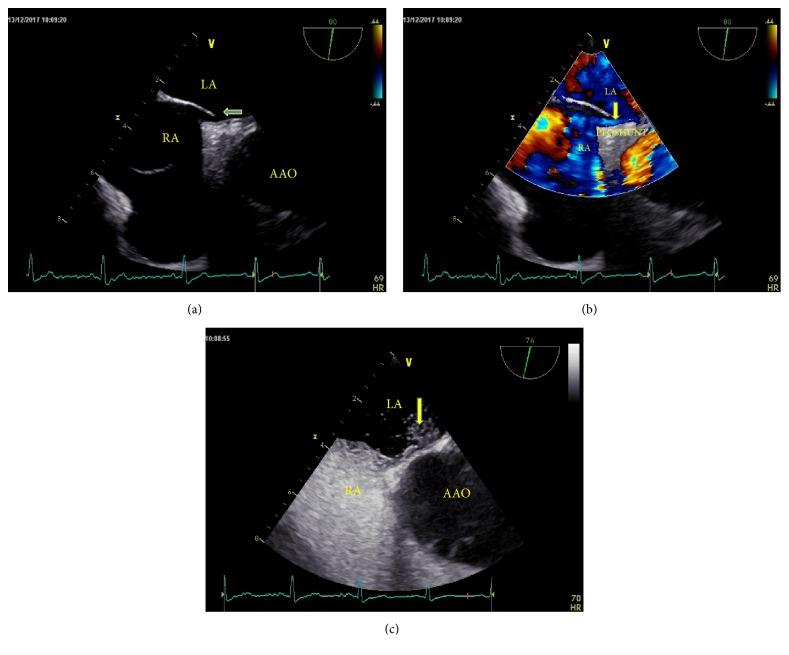

To compare the sensitivity and specificity of modified and traditional methods of contrast echocardiography of the right portion of the heart in patients with a suspicion of patent foramen ovale (PFO).

The study population consisted of 506 patients with high clinical suspicion of PFO. The traditional Valsalva maneuver consists of expiration against a closed glottis after a full inspiration. A modified Valsalva maneuver was performed with a handmade pressure monitoring device, which measured pressure during performance of the Valsalva maneuver. Modified and traditional methods of contrast echocardiography were performed among all patients. Contrast transesophageal echocardiography (TEE) was regarded as the gold standard.

A total of 279 patients with PFO were confirmed by TEE. 259 cases (sensitivity: 92.83%) were detected by a modified method of contrast echocardiography of the right portion of the heart, while 234 cases were detected using the traditional method (sensitivity: 83.87%). The sensitivity of modified contrast echocardiography of the right portion of the heart was significantly higher than that of the traditional method (92.83% vs. 83.87%, =0.001). However, there was no significant difference in the specificity of the two methods for the diagnosis of PFO (97.35% vs. 96.03%, =0.431). Additionally, the results of semiquantitative evaluation of PFO using modified method failed to show a more positive rate than shown by the traditional method (Z=-1.782, =0.075).